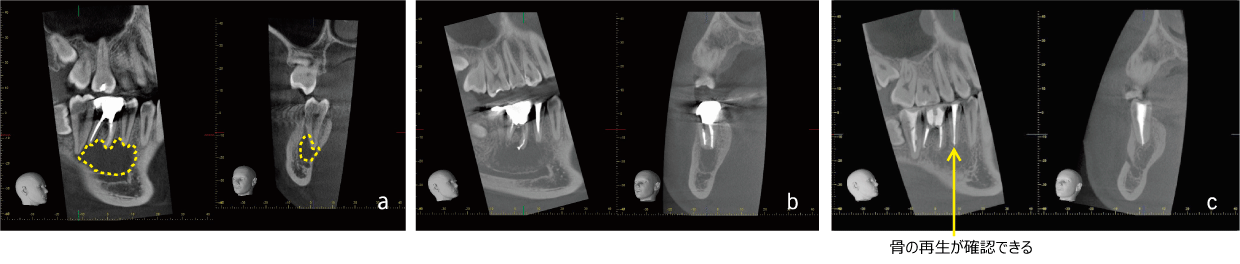

A 6 root tip lesion had spread buccally, perforated the buccal bone, and formed a thin canal with an opening diameter of approximately 3.7 x 5.8 mm. Bleeding was observed from the distal root canal foramen, and the probing depth was within 3 mm. After root canal formation, EMAT was performed and the canal was filled immediately. Although there was a slight enlargement of the periodontal lumen on the distal side of the centorhombic root, the bone beam structure was homogenized, and a continuous alveolar hard line was observed, showing an almost normal image.

It is known that the thin hole usually heals after appropriate root canal treatment and resolution of periapical inflammation. However, when the bone wall defect is large, bone formation is insufficient and connective tissue invades the defect, resulting in some cases where bone defects remain on radiographs despite the absence of inflammation.

In this case, a large bone wall loss was observed on the buccal side, but bone formation was observed one month later, suggesting that EMAT may have exerted its healing-promoting effect.